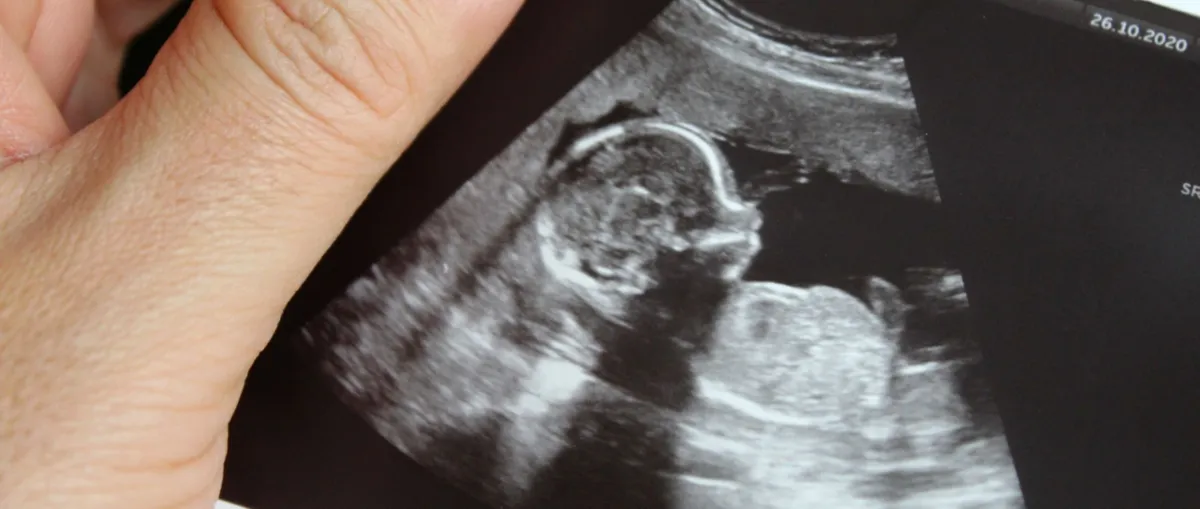

تعتبر زيارة الطبيب بصفة منتظمة خاصة في بداية الحمل خطوة بالغة الأهمية، حيث تساعد في التعرف إلى المشاكل الصحية في وقت مبكر، وتتيح بذلك فرص العلاج قبل تفاقم الوضع الصحي، فالتشخيص المبكر والعلاج المبكر يمكن أن يشفي الحامل من مشاكل وأمراض كثيرة ويمنع حدوث مضاعفات أخرى، وبذلك تنعم الحامل بحياة صحية أكثر أماناً.

كما ينصح بالاستمرار في الحصول على رعاية صحية منتظمة قبل الولادة، ويفضل ألا تقل عدد زيارات الطبيب عن 4 زيارات خلال فترة الحمل، كما ينصح بزيادة عدد الزيارات في حالة ظهور أية مشاكل في الحمل. كذلك فإن اتباع نصائح الطبيب والالتزام بالعلاج والنصائح الطبية جميعها أمور مهمة للحفاظ على سلامتك وسلامة طفلك.